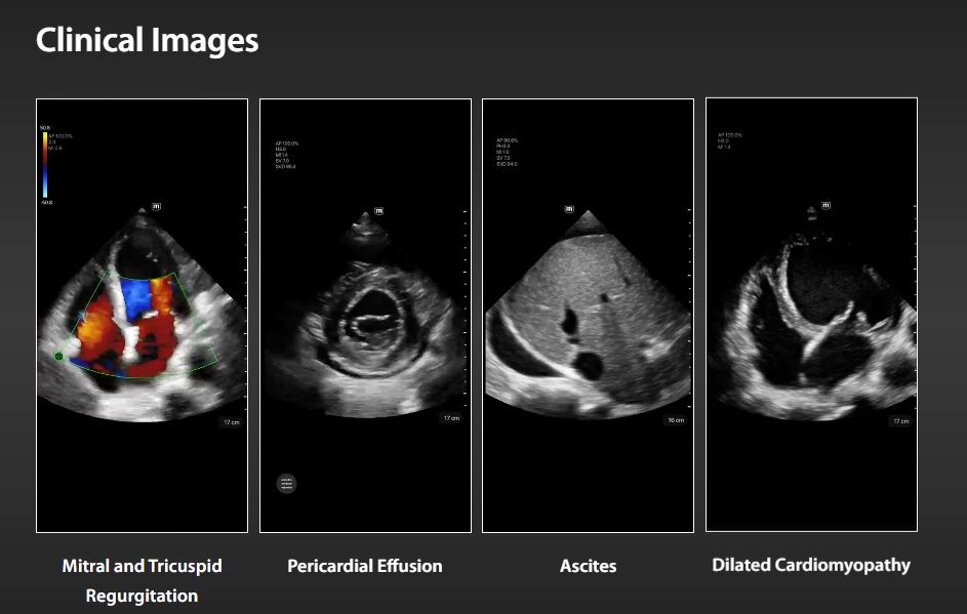

L'ecografia Point of Care (POCUS) è stata affermata come una tecnica di imaging essenziale per ambienti frenetici. Poiché le applicazioni cliniche di POCUS continuano ad espandersi, vi è una crescente domanda di dispositivi ecografici portatili di alta qualità.

TE Air, il sistema ecografico portatile wireless di nuova generazione di Mindray, è progettato per soddisfare questi requisiti clinici più elevati, come l'emergenza e la terapia intensiva. Combinando funzionalità premium con un'esperienza wireless, una connettività efficiente e un design robusto per ambienti imprevedibili, il sistema ecografico portatile wireless TE Air aiuta a migliorare la fiducia e l'efficienza dei medici in modi senza precedenti.